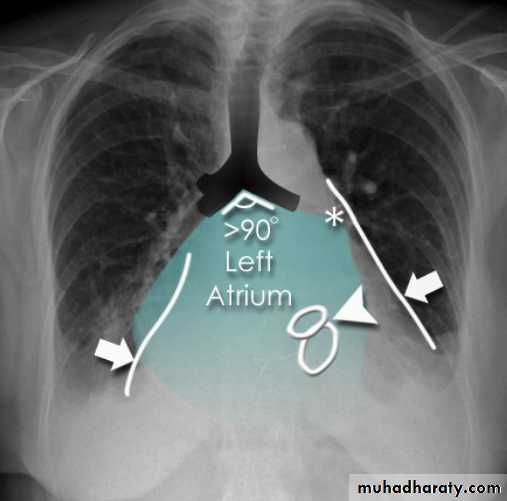

Radiographic featuresPlain film

Typical radiographic features of mitral regurgitation include :

frontal projection

left atrial enlargement

convexity or straightening of the left atrial appendage just below the main pulmonary artery (along left heart border)

double density sign: the right side of the enlarged left atrium pushes into the adjacent lung and creates an addition contour superimposed over the right heart

elevation of the left main bronchus and splaying of the carina

upper zone venous enlargement due to pulmonary venous hypertension

left ventricular enlargement is also eventually present due to volume overload

Features of pulmonary oedema may also be present.